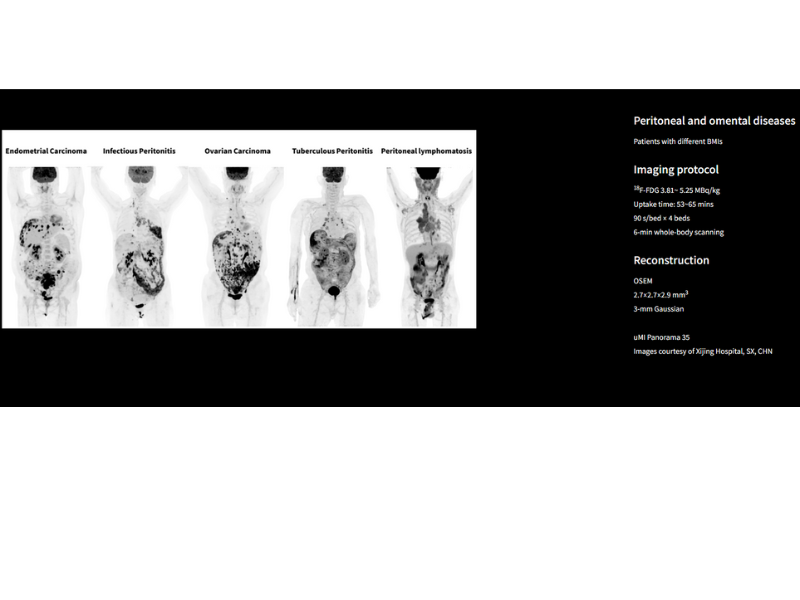

The high-resolution system with 194-ps TOF performance delivers execptional image quality for peritoneal and omental diseases.